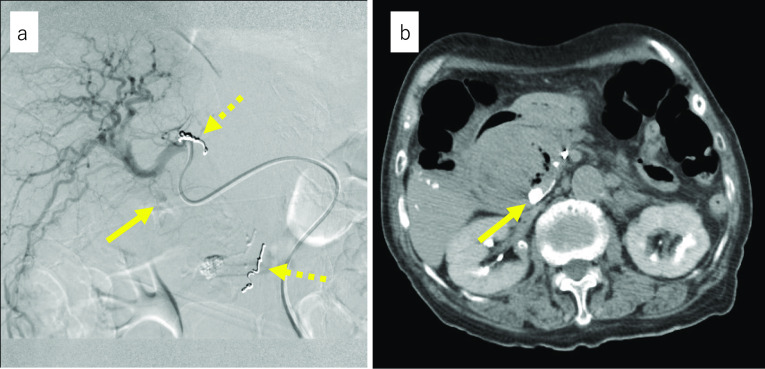

Enhanced CT at our hospital showed high-density collection, which indicated rather flesh blood and pseudoaneurysm within the cystic lesion measuring 50 mm in the pancreatic head (Fig. 1a). The gallbladder had already been resected, and the intestinal tract, which was suspected to be the lifted jejunum, was adjacent to the cystic lesion (Fig. 1b). Angiography was reperformed for diagnosis and treatment at our hospital on the day of admission, and extravasation from the pseudoaneurysm measuring 11 mm in the peribiliary vascular plexus (PBP) branched from the proper hepatic artery was recognized. The PBP was embolized as selectively as possible with n-butyl-2-cyanoacrylate (NBCA), and hemostasis was obtained (Fig. 2a, b). The clinical course after TAE was uneventful and no liver dysfunction occurred. Based on the CT findings, interventional radiology (IVR), and considerations that IDS was the standard operation for CBD in the 1950s, the cause of hemorrhage shock was determined to be due to hemobilia of the remaining dilated bile duct after IDS.

The purposes of treatment for hemobilia are hemostasis and maintaining bile flow. The latter is especially important because of the development of cholangitis or pancreatitis due to blood clots in the biliary tract [ref. 8]. Various treatments for hemobilia, including follow-up observation, endoscopic approaches, and surgery, depend on the cause or degree of hemorrhage. IVR, as a diagnostic and treatment modality, is effective for patients for whom hemodynamics are unstable due to active hemorrhage [ref. 7]. In our case, IVR was chosen because the patient was in hemorrhagic shock. Generally, the blood flow of the extrahepatic bile duct is supplied from the left and right hepatic arteries, cystic artery, proper hepatic artery, and posterior superior pancreaticoduodenal artery. These arteries form the complex PBP [ref. 9]. Additionally, considering that extravasation was not observed in the supplying arteries to the pancreatic head from the pancreaticoduodenal arcade, the patient was diagnosed not with hemorrhage from pseudopancreatic cysts but with hemorrhage in the remnant dilated bile duct lumen. Furthermore, in our case, extravasation occurred from a pseudoaneurysm developed in the branch of the proper hepatic artery. Although selective TAE was successfully performed and hemostasis was obtained, there was concern about the possibility of rehemorrhage from the PBP. Therefore, extrahepatic bile duct resection with bilioenteric reanastomosis was performed to prevent rehemorrhage.